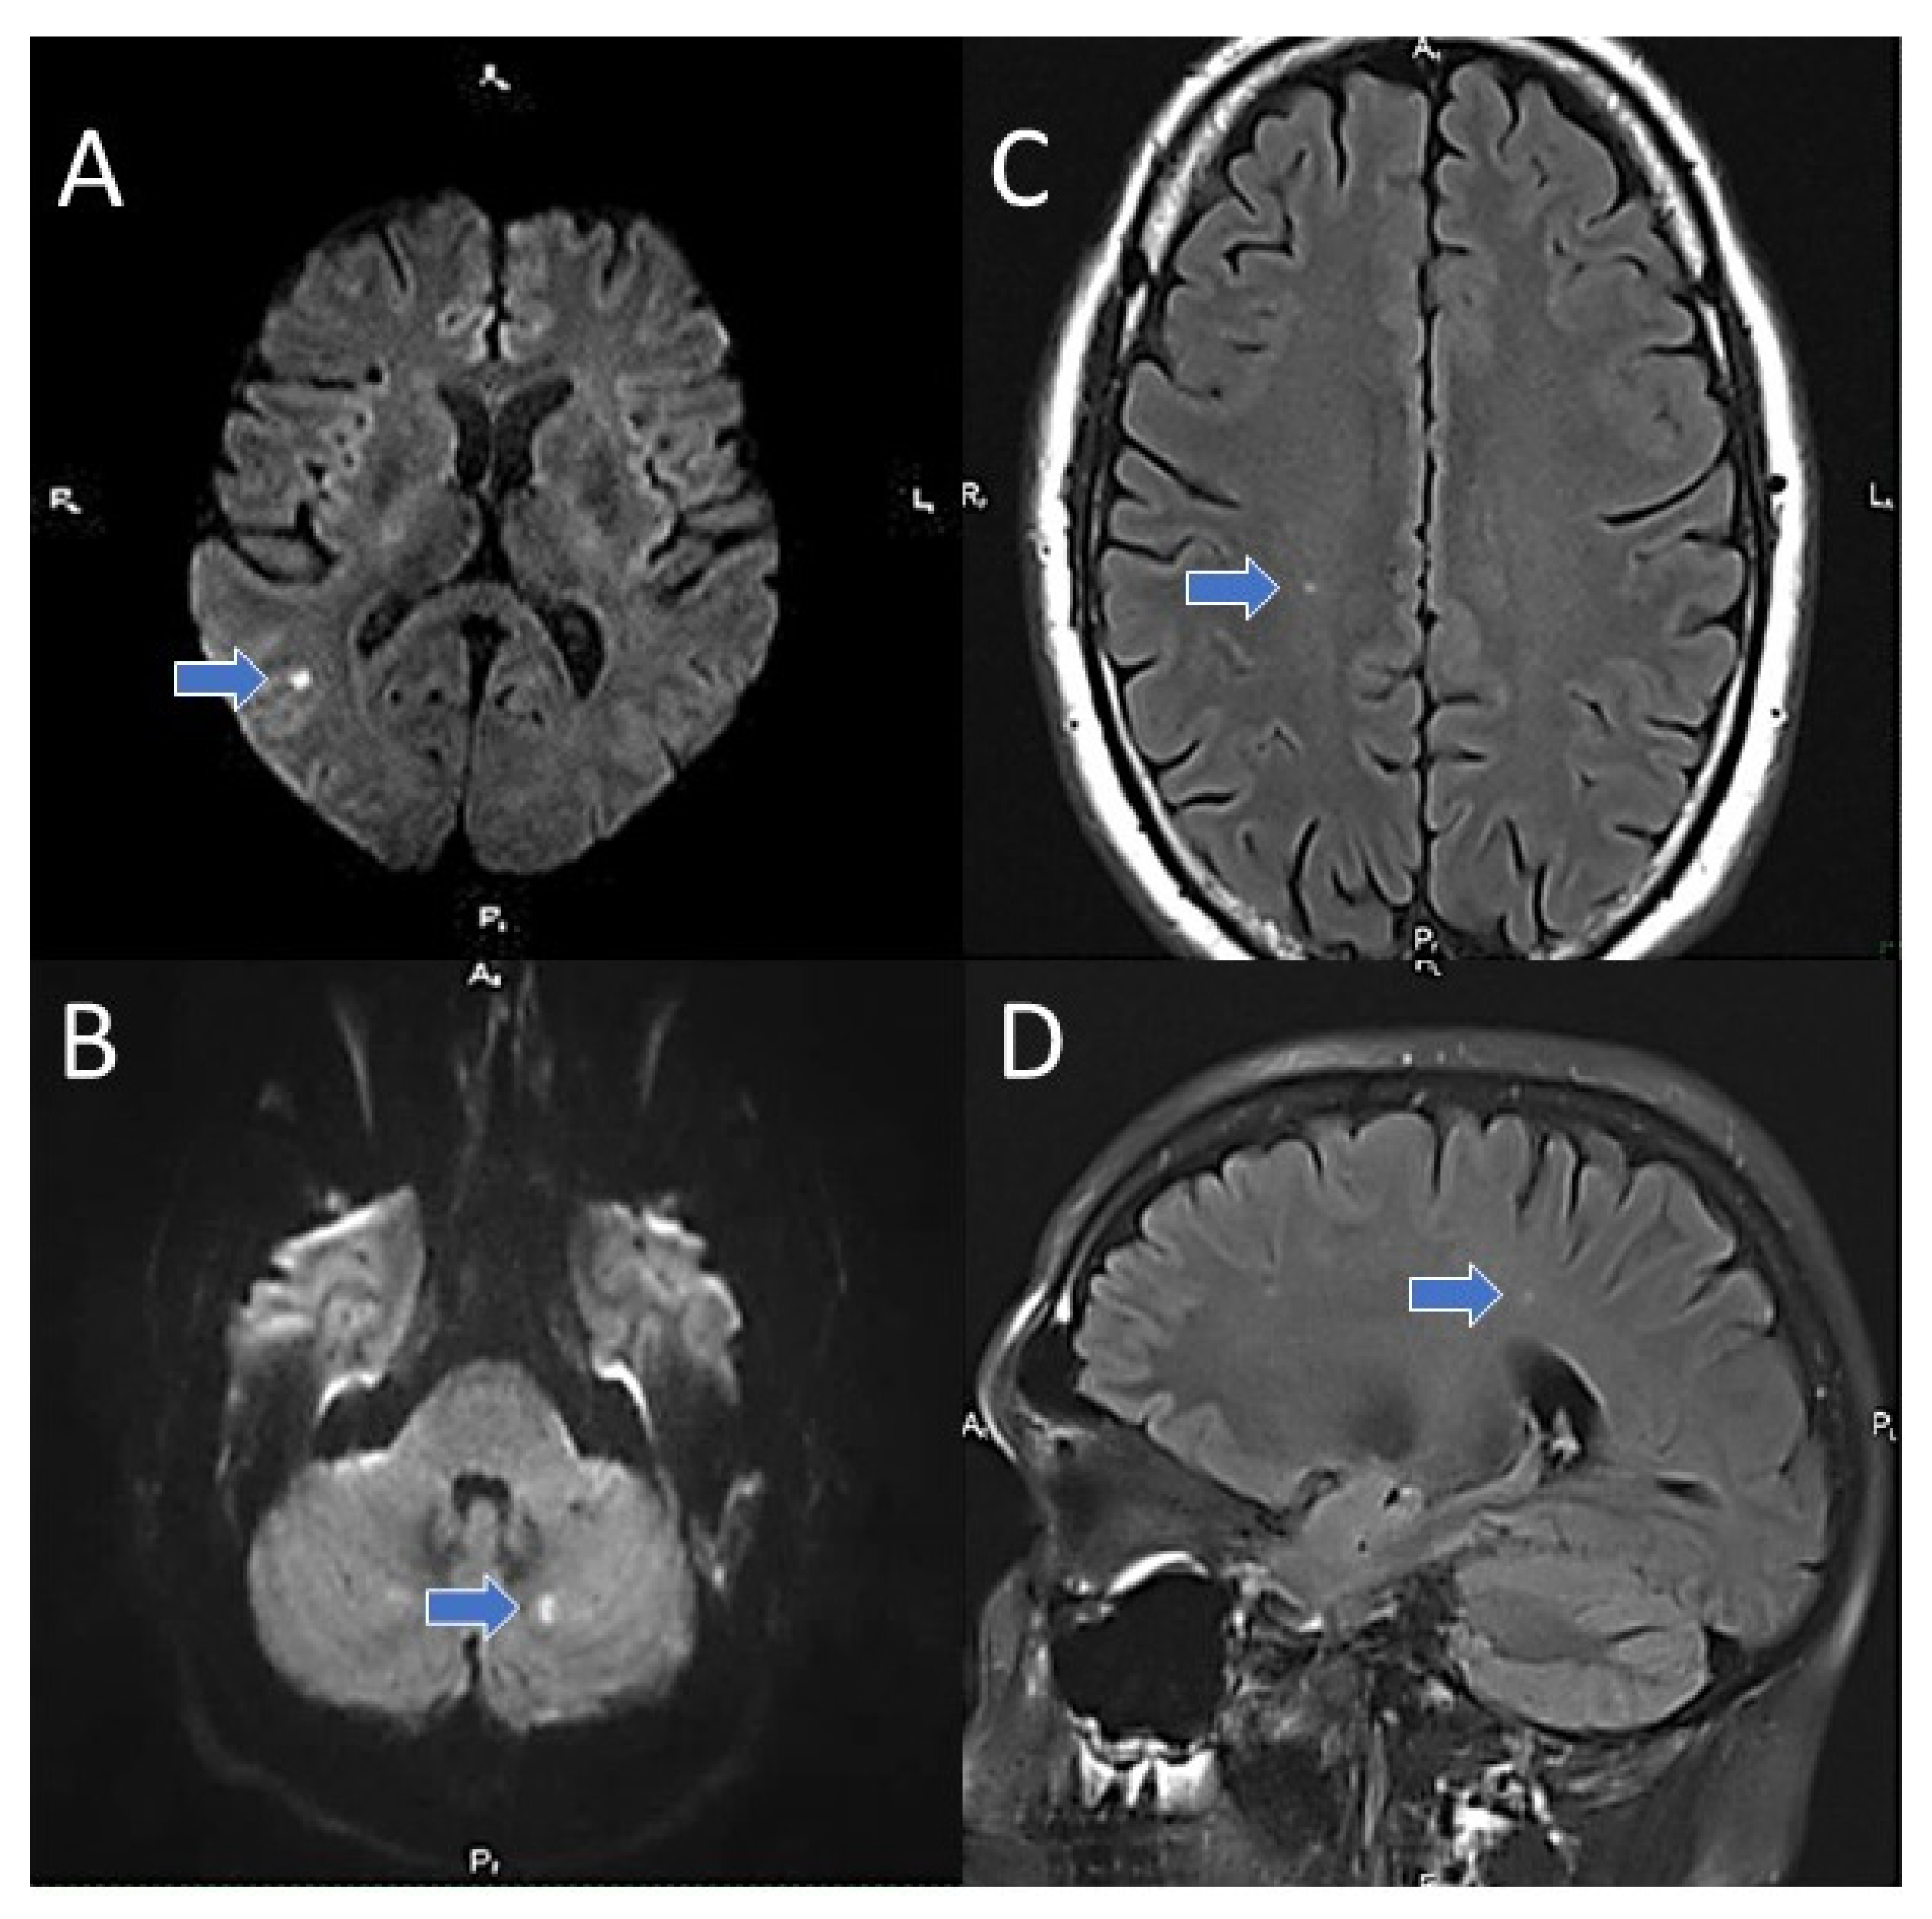

3.2. Prevalence of CBIs